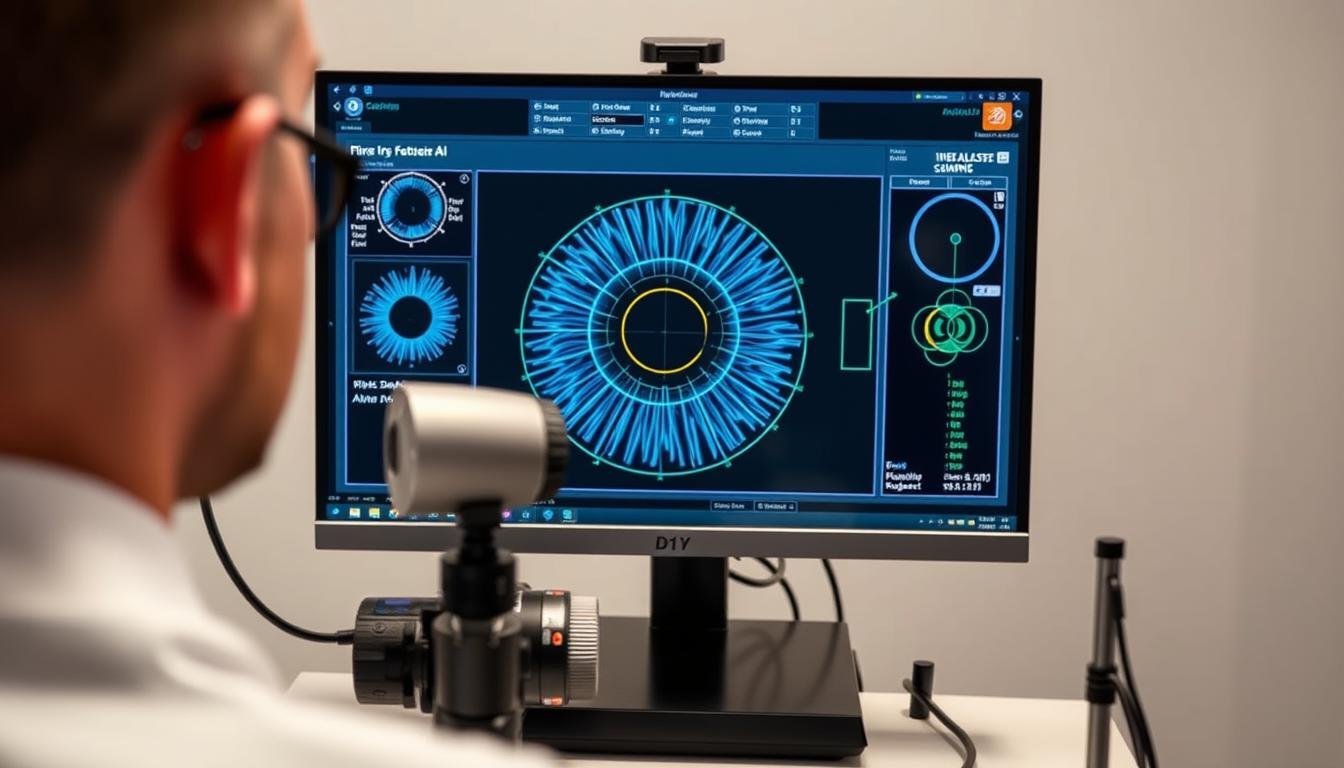

Integración de la lectura del iris con tecnologías modernas

Software avanzado de análisis del iris con capacidades de inteligencia artificial

Las cámaras digitales especializadas para la lectura del iris pueden capturar imágenes con una resolución de hasta 24 megapíxeles, revelando detalles microscópicos del iris imposibles de observar a simple vista. Estas cámaras incluyen iluminación LED específica que minimiza los reflejos y optimiza la visualización de las estructuras del iris.

Software de análisis especializado

Los programas informáticos modernos para la lectura del iris pueden procesar imágenes digitales, segmentar automáticamente las zonas del iris y detectar patrones específicos. Algunos sistemas avanzados utilizan algoritmos de aprendizaje automático para identificar correlaciones entre ciertos marcadores del iris y condiciones de salud específicas.

La integración de estas tecnologías ha permitido superar algunas de las limitaciones tradicionales de la lectura del iris, como la subjetividad en la interpretación y la dificultad para documentar cambios sutiles a lo largo del tiempo. Ahora es posible realizar análisis más objetivos y reproducibles.

Los avances en inteligencia artificial prometen llevar la lectura del iris a un nuevo nivel. Los sistemas de IA están siendo entrenados para reconocer patrones complejos en el iris y correlacionarlos con datos clínicos, potencialmente mejorando la precisión diagnóstica y descubriendo nuevas asociaciones entre los marcadores del iris y las condiciones de salud.